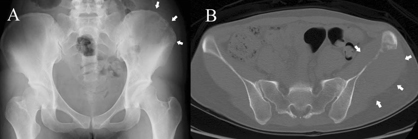

Magnetic resonance imaging should be the imaging method of the first choice. It is efficient in verifying suspected malignancy and can provide extensive anatomical information regarding the primary tumor’s location and its relationship to the FN and surrounding tissues [3],[4]. In addition to the well-known signs of parotid malignancy, such as poorly defined borders, large tumor size with noticeable invasiveness, irregular shape, infiltration of extra-parotid lymph nodes, and low to moderate signal intensity on T2-weighted images, relatively large tumors with central necrosis is a useful imaging feature of SCC originating in the parotid gland (Figure 1) [5],[6].

Figure 1: A 62-year-old male with primary parotid squamous cell carcinoma in the left parotid gland. Magnetic resonance images were acquired using a 3.0 T MRI machine. Axial T2WI (A) and T1WI (B) show an irregular mass involving the left parotid gland and masseter muscle, with the tumor showing a slightly low signal and multiple small focal areas of markedly high signal on T2WI (arrow). Enhanced axial (C) and coronal (D) T1WI show inhomogeneous enhancement with necrotic areas in the center (arrow).